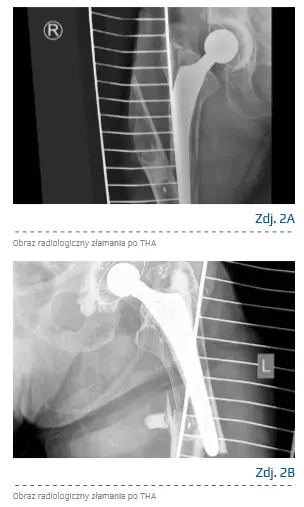

Złamania okołoprotezowe kości udowej są powikłaniami sprawiającymi znaczne trudności w leczeniu [24]. Zgodnie z danymi z Amerykańskiego Rejestru Aloplastyk z 2016 r. 4,4% operacji rewizyjnych zostało wykonanych z powodu złamania [4]. Zaznacza się znaczna dysproporcja pomiędzy występowaniem złamań po operacjach pierwotnych i rewizyjnych. Dla THA pierwotnej ryzyko jest oceniane na ok. 1%, dla rewizji jest to już 4,4% [25].

Złamania okołoprotezowe można podzielić z uwzględnieniem czasu wystąpienia, lokalizacji oraz stopnia stabilności protezy. Wyróżnia się złamania występujące śródoperacyjnie, do których najczęściej dochodzi podczas implantowania protez bezcementowych [26]. Kolejną grupą są złamania pooperacyjne (wczesne oraz późne).

Wśród czynników ryzyka złamań okołoprotezowych wymienia się: zmniejszoną wytrzymałość tkanki kostnej (osteopenia, osteoporoza), wcześniejsze operacje proksymalnego końca kości udowej, osteolizę i aseptyczne obluzowanie komponenty [27], a także reumatoidalne zapalenie stawów oraz przewlekłą steroidoterapię [28]. Operacje po takich złamaniach są zabiegami podwyższonego ryzyka, m.in. ze względu na znaczną rozległość operacji, dużą utratę krwi i ryzyko wystąpienia powikłań [29].

Są również trudne technicznie ze względu na częste współistnienie złamania, obluzowania implantu czy utraty tkanki kostnej [30]. Wybór odpowiedniej metody leczenia jest uzależniony od stabilności implantów i lokalizacji złamania. W większości przypadków stosuje się leczenie z repozycją otwartą i wewnętrzną stabilizację złamania z jednoczesną rewizją lub bez niej. Najczęściej wykorzystywaną metodą leczenia złamań ze stabilnymi komponentami protezy jest zespolenie złamania płytami, które mogą być konwencjonalne lub blokowane z wieloosiową stabilizacją. Zwiększenie stabilności można uzyskać poprzez zastosowanie alograftu [28, 31, 32]. Część płyty pozwala na wykonanie dodatkowego wzmocnienia pętlami z drutu [26]. Powikłania leczenia złamań okołoprotezowych są częste – szacuje się, że występują w 26–43% przypadków [33]. Zgodnie z danymi złamania okołoprotezowe są związane ze znacznym pogorszeniem funkcjonalności pacjentów [34] i zwiększeniem śmiertelności [35]. Są one także zjawiskiem negatywnym w aspekcie ekonomicznym, ponieważ leczenie i rehabilitacja złamań generuje znaczne koszty [24, 36]. Przykładowe obrazy radiologiczne złamania po THA przedstawiono na zdjęciach 2A i 2B.